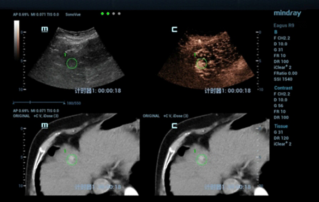

![microwave-ablation-for-recurrent-liver-cancer-assisted-by-fusion.thumb.319.319 Ultrasound Journal 1: Mindray "Fusion imaging"? ??? ??? ?? Micowave Ablation ??? ??]() Ultrasound Journal 1: Mindray "Fusion imaging"? ??? ??? ?? Micowave Ablation ??? ????? ?? | ??? ??? | ?? ?? 2022-11-15

Ultrasound Journal 1: Mindray "Fusion imaging"? ??? ??? ?? Micowave Ablation ??? ????? ?? | ??? ??? | ?? ?? 2022-11-15 -